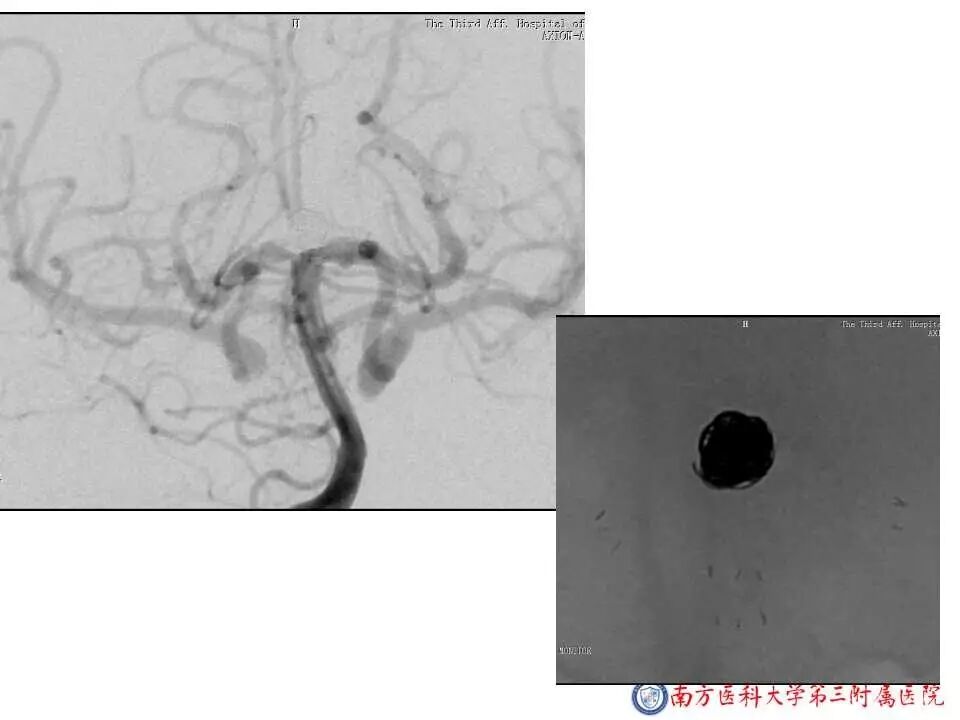

今天为大家分享的是“强生医疗CNV-神经介入专栏”第二十五期,由南方医科大学第三附属医院神经外科主任黄理金教授带来的“Enterprise支架辅助栓塞动脉瘤的优势”精彩讲课视频及PPT,欢迎观看。文章仅代表作者个人观点,如有不同见解,欢迎同道斧正!